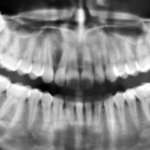

Diagnostica differenziale delle lesioni pigmentate del cavo orale Premium

Le varie localizzazioni e manifestazioni delle pigmentazioni della mucosa orale rendono difficile distinguere quelle attribuibili a malattie sistemiche, a malattie infiammatorie, a neoplasie, a...